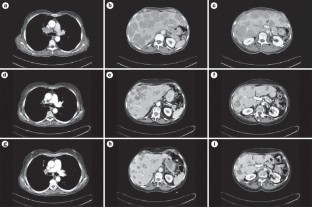

Background. A 61-year-old patient with no relevant medical or family history presented with a 2 month history of refractory dry cough that led to the diagnosis of typical carcinoid tumor of the lung metastatic to the mediastinal lymph nodes and liver. She initially received a long-acting somatostatin analog (octreotide) and chemotherapy with cisplatin and etoposide, which was ineffective.

Investigations. Physical examination, laboratory test, chromogranin A test, CT scan, 111In-diethylenetriaminepentaacetic acid (DTPA)-octreotide scan, 18F-FDG-PET scan, fine-needle and tissue core liver biopsies.

Diagnosis. Pulmonary spindle-cell carcinoid tumor with metastases to mediastinal lymph nodes and liver.

Management. Systemic treatment with oral capecitabine (1,500 mg/m2 daily from day 1 to day 21) and intravenous liposomal doxorubicin (10 mg/m2 on days 1, 8 and 15), both repeated every 4 weeks, administered concomitantly with long-acting octreotide 30 mg every 3 weeks. The patient achieved a significant and long-lasting response with the combination of capecitabine and liposomal doxorubicin. She reported no severe adverse effects.